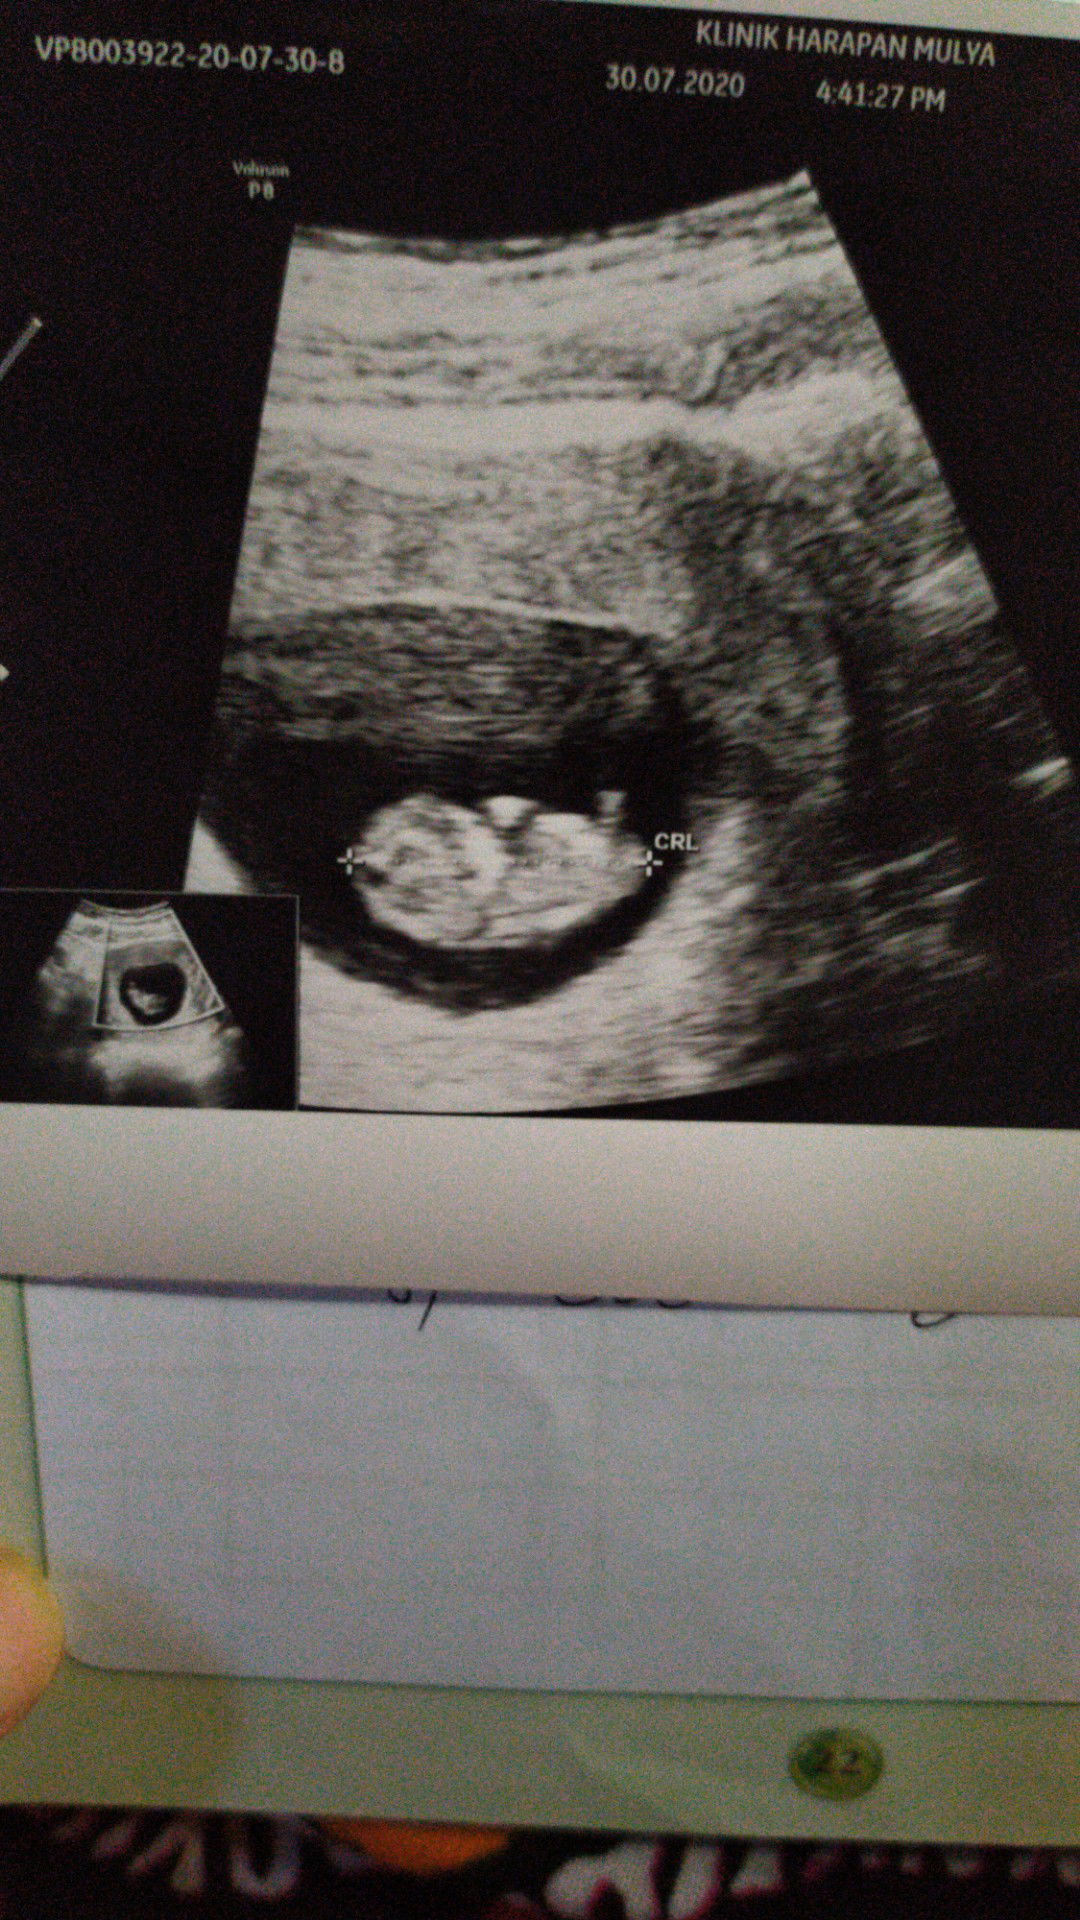

Bun biasanya kalau cek detak jantung janin lewat doppler itu kedengerannya d usia berapa minggu ??

Soalnya saya udh 10minggu tpi blom kedengeran pas dicek d bidan pake doppler